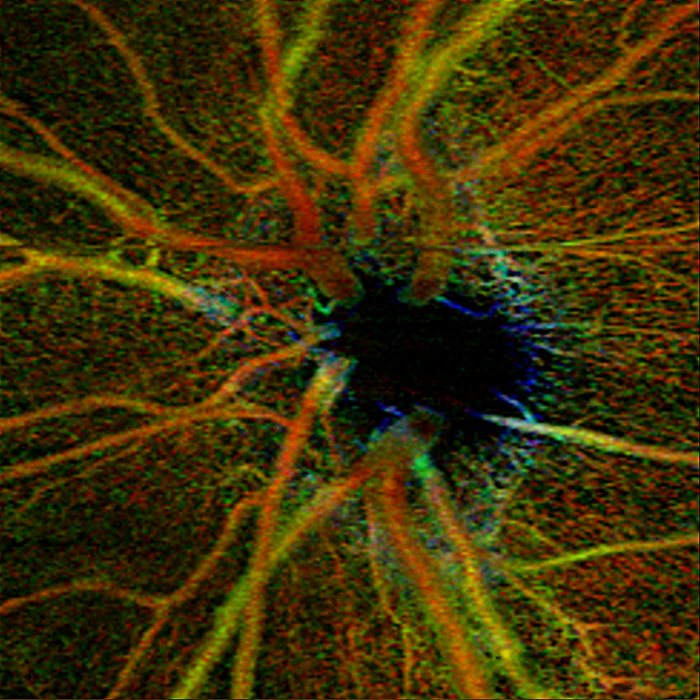

Neuronal Image Sequence

Cover of European Journal of Neuroscience